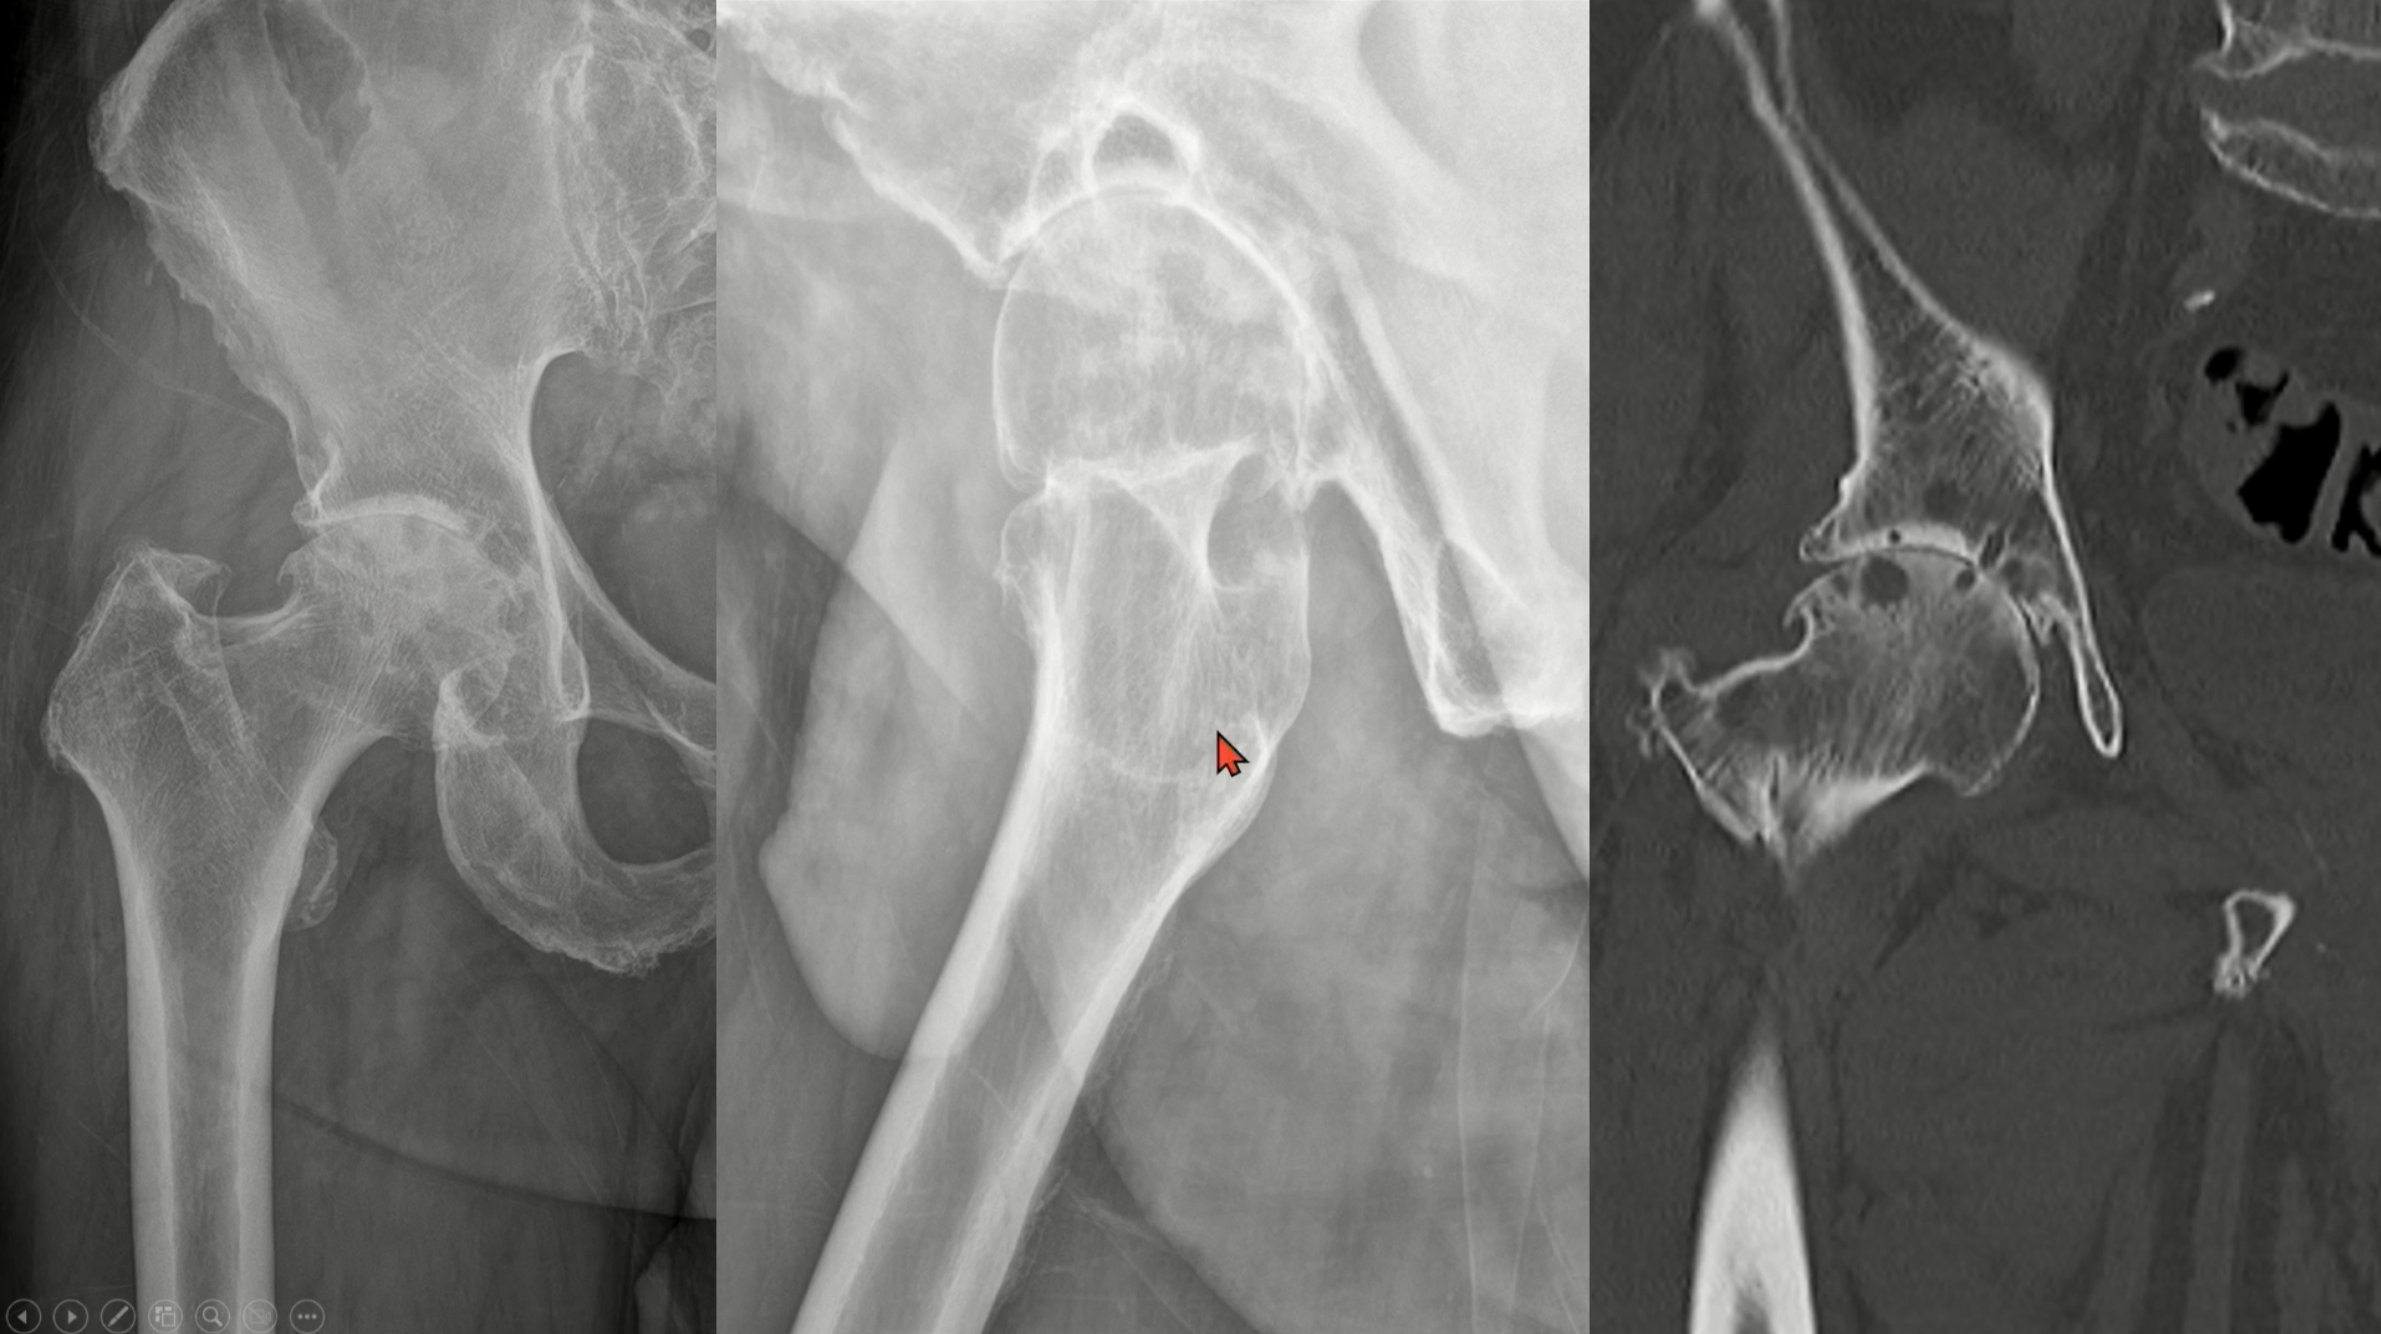

실제 진행된 고관절 관절염의 영상입니다.

joint space narrowing, subchondral screlosis and cystic change, osteophyte, superior migation을 보이고 있습니다.